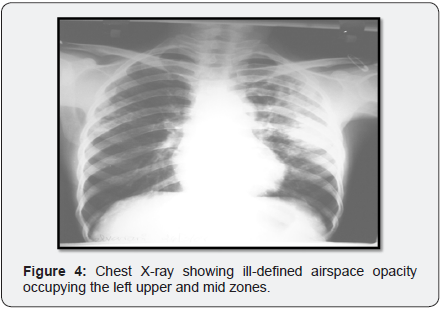

Chest x-ray (Figure 4) showed initially showed ill-defined air space opacity occupying the left upper and mid zones for which anti tuberculosis treatment started in Erode. Later X-ray (Figure 5) showed progression of consolidation in left side with appearance of well-defined oval mass like lesion with positive air crescent sign (Halo sign) in right upper zone.

Expectorated sputa were positive on Gram staining for branching, beaded, filamentous bacteria (Figure 6) and negative on stain for Pneumocystis and AFB but later positive for modified acid-fast staining. The patient was continued on high dose oral Trimethoprim/sulfamethoxazole with continued clinical improvement and was discharged from the hospital on that regimen. Follow up X-ray showed improvement (Figure 7).